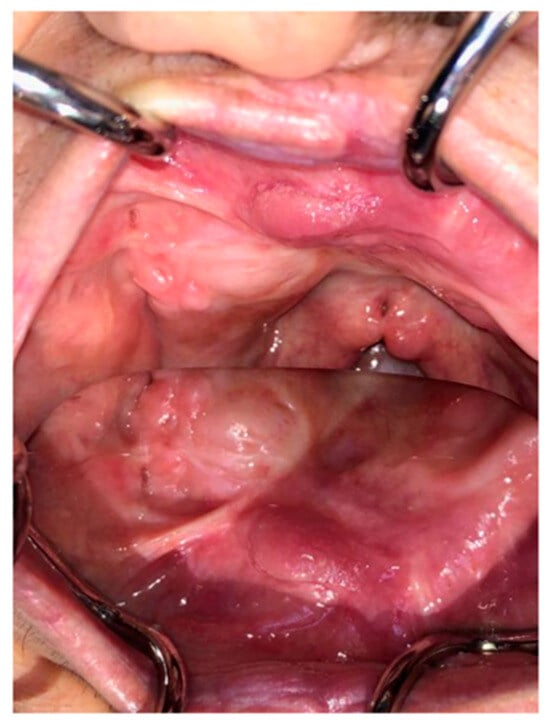

The Use of Dorsum of Tongue Flap for the Closure of an Oroantral Fistula with no Contiguous Tissue Available to Be Used: Surgical Procedure and Case Report †